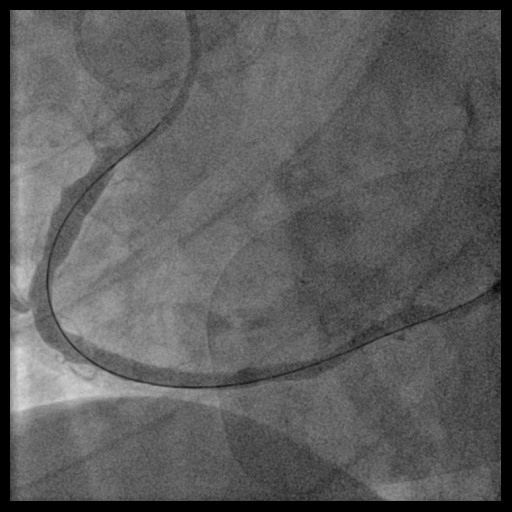

During this emergency catheterization, the right radial artery was accessed using a 20-gauge needle. A 6 Fr in 5 Glidesheath Slender® (Terumo Corp., Tokyo, Japan) was inserted. Coronary angiography was performed using Terumo 5 Fr Judkins catheters, revealing in-stent total occlusion of the RCA and patent left coronary artery (LCA).

In anticipation of a high thrombus burden, intracoronary Tirofiban was given to mitigate thrombotic risks. The Terumo 6 Fr in 5 Glidesheath Slender was exchanged for a 7 Fr in 6 Glidesheath Slender to accommodate larger catheters while preserving radial artery access. Using a 7 Fr SAL 1.0 guiding catheter (Medtronic, USA), the Fielder FC 0.014” × 180 cm wire (ASAHI Intecc, Japan) was advanced to the distal RCA. Despite GuideLiner (Teleflex, USA) support, the Terumo Eliminate aspiration catheter could not advance beyond the mid-RCA. StentBoost imaging revealed the wire had wound along the aneurysmal vessel wall and passing through a previous stent’s strut. Attempts to reshape the wire tip for re-entry into the stent center were unsuccessful. Although stent crushing was considered, navigating the wire through the stent without damage was prioritized. An Euphora balloon (2.0 × 20 mm) was inflated at 2 atm to seal the gap between the stent and vessel wall, enabling the passage of a Runthrough NS Floppy wire into the distal RCA. IVUS confirmed the wire’s position within the stent, which remained intact. The wire was exchanged for an ASAHI Sion Blue Extra-support wire with a Caravel microcatheter. Thrombus aspiration was completed using the Eliminate catheter. Post-dilatation was performed with a Conqueror NC balloon (4.00 × 20 mm, APT Medical), followed by NC Emerge and Accuforce balloons (4.5-6.0 mm). IVUS confirmed excellent stent apposition, and TIMI 3 flow was achieved.